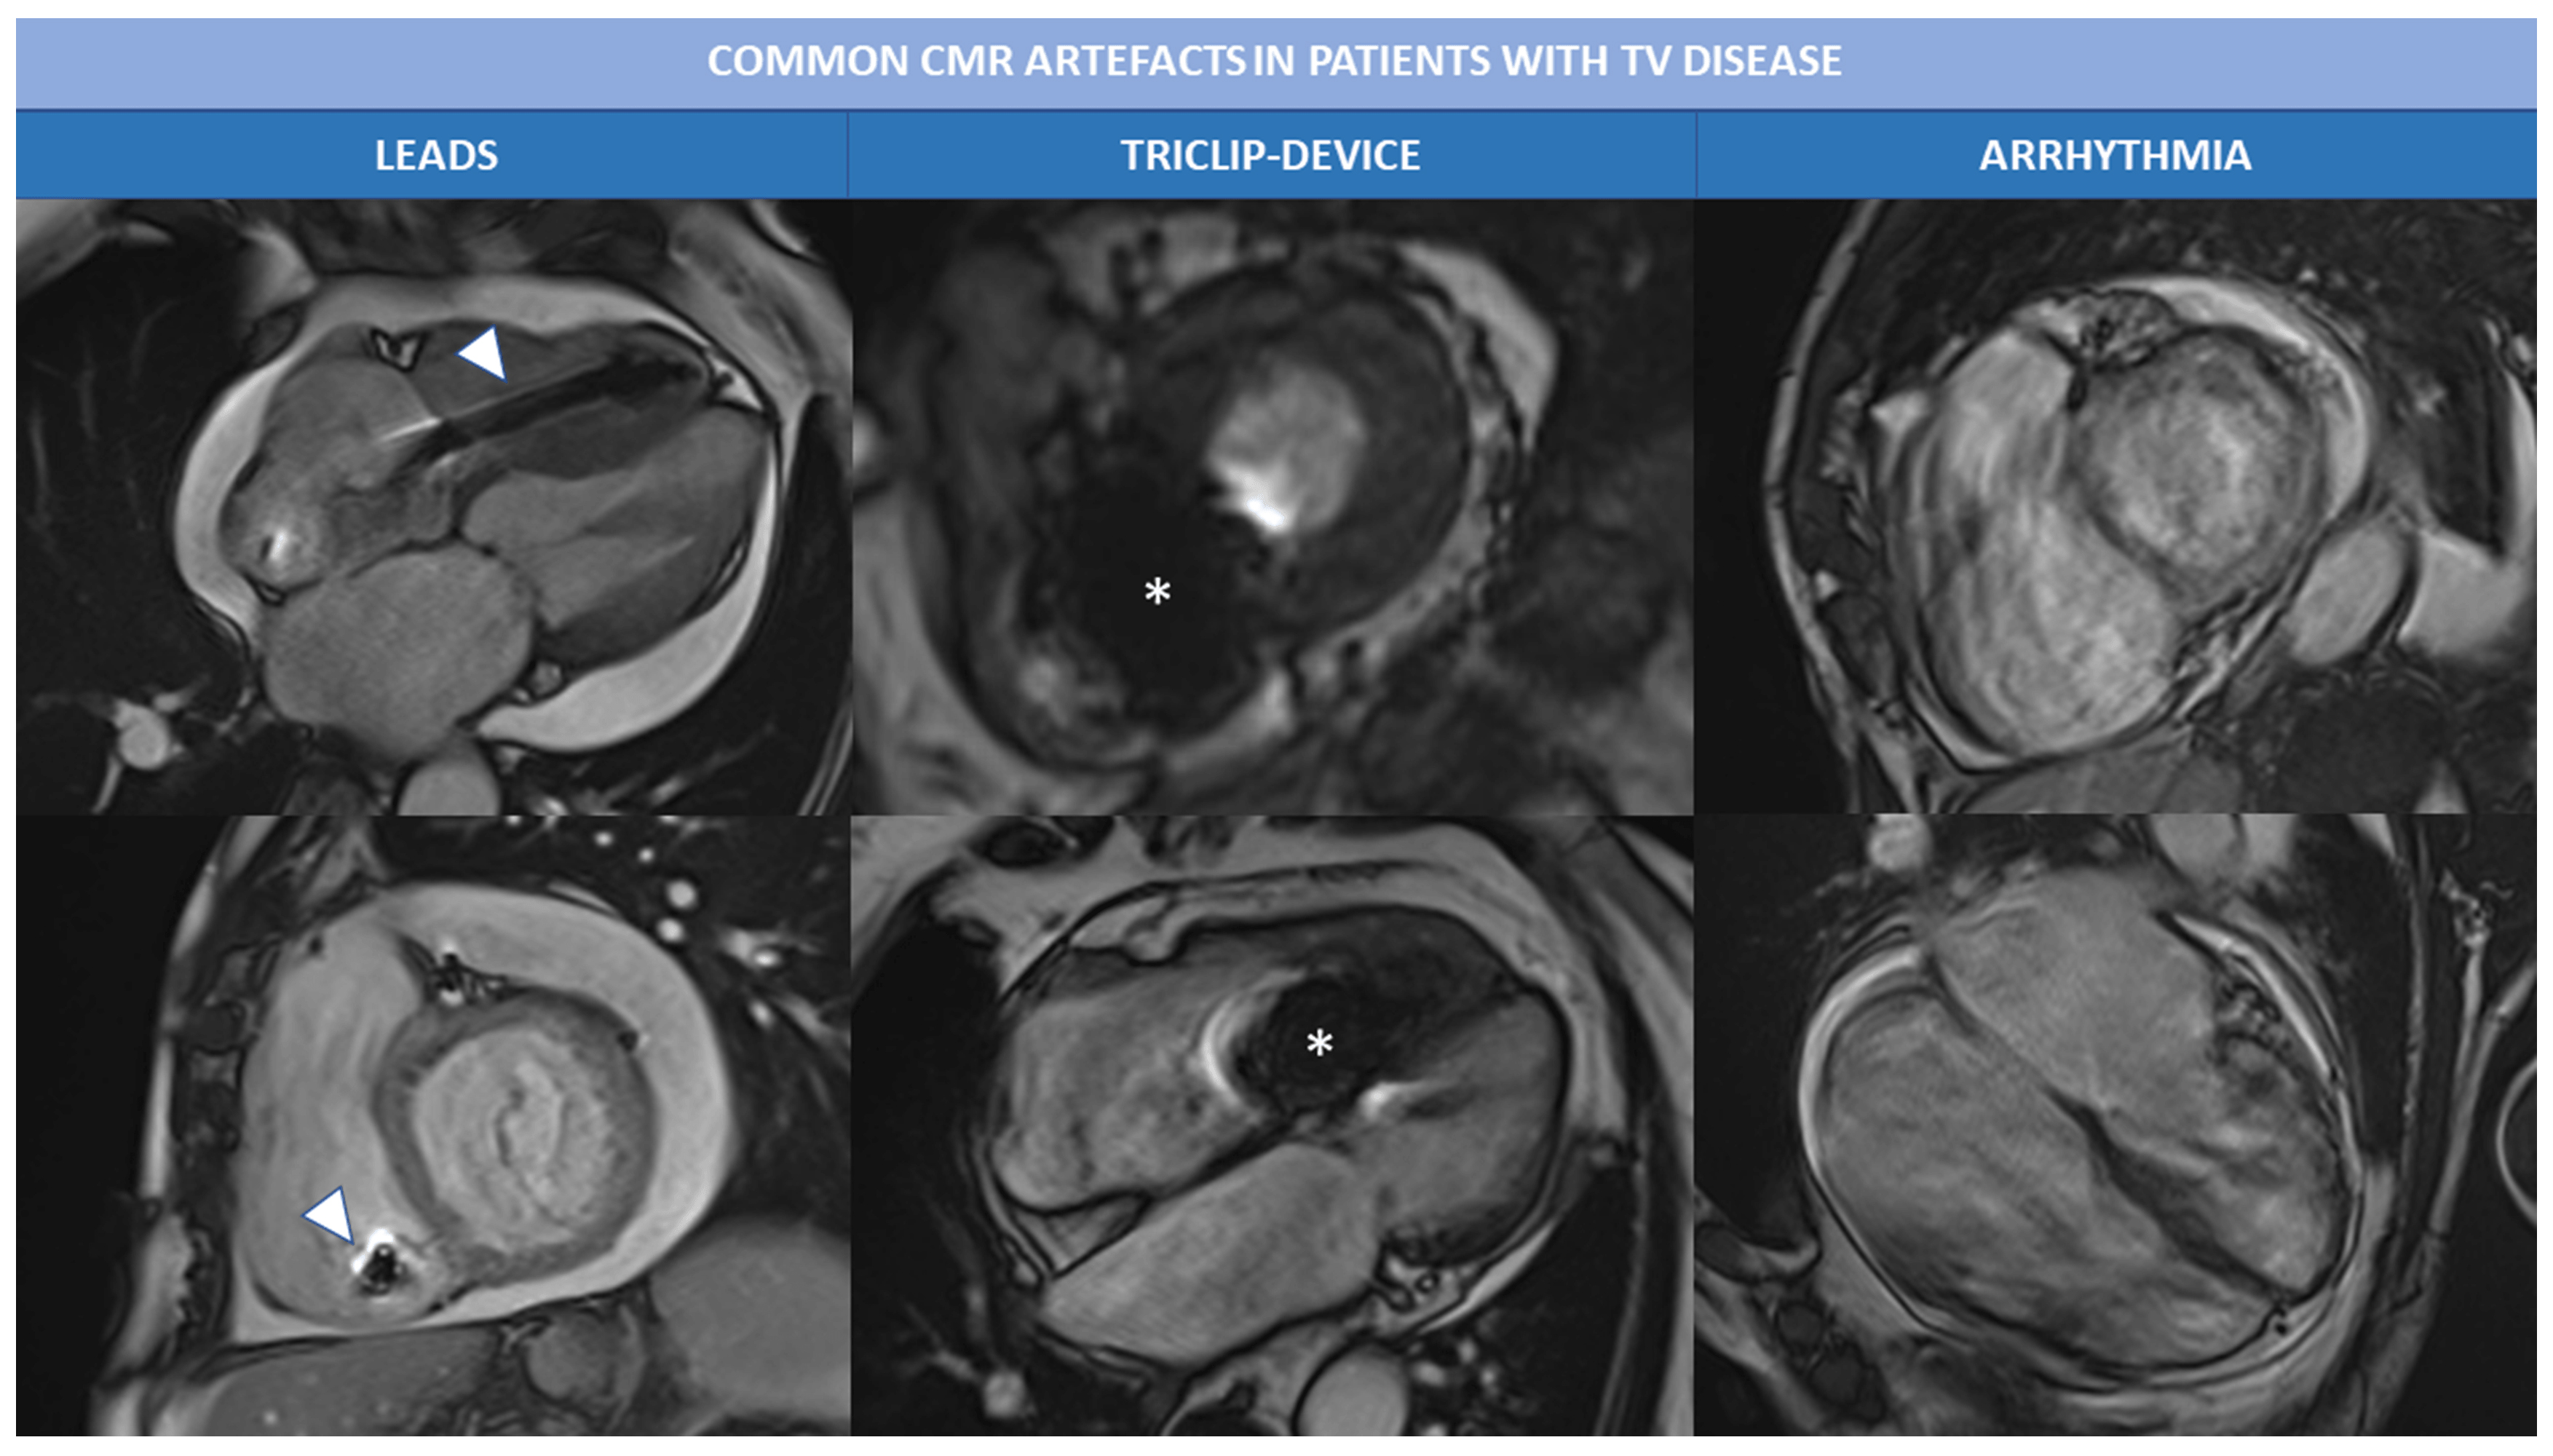

In patients with TR the exam quality can be affected by the presence of arrythmia (atrial fibrillation is the most common) and/or PM leads or devices (like TriClip). Most common artefacts that occur during Cine bSSFP sequences are presented in Fig. 4. In case of extreme irregular RR intervals, prospective triggering or real-time free-breathing cine sequences can be acquired to avoid artefacts related to HR variability. Leads and other intracardiac devices are responsible of metallic artefacts than can compromise image quality, above all of bSSFP sequences; in this case the use of cine fast-spoiled gradient, instead of bSSFP, can reduce magnetic susceptibility artefacts.

Fig. 4.Common CMR artefacts in patients with TV disease. Magnetic susceptibility and metallic artefacts are frequent in patients with TR; they are caused by the presence of ferromagnetic components of PM leads (arrowheads) or triclip device (*) and can affect image quality. Arrhythmias, like atrial fibrillation is often associated with severe TR and can cause motion artefacts, as shown in the right column. Abbreviations: CMR, cardiac magnetic resonance; PM, pace maker; TR, tricuspid regurgitation; TV, tricuspid valve.